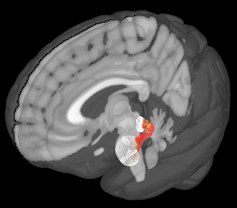

There are two major regions in what brain scientists call the “offspring care neural network,” evolutionarily old structures deep in the brain called the amygdala and the periaqueductal gray.

The periaqueductal gray is another small u-shaped structure at the base of the brain. It plays an important role in controlling basic behaviors like the impulse to cuddle a baby or the instinct to avoid predators.

We found some interesting effects while reviewing images captured during this experiment. Most notably, the amygdalas and their periaqueductal gray were more active for kidney donors than people in our control group, with stronger reactions to fearful and distressed stimuli.

What we found suggests that these two regions might be communicating or otherwise working together. We further tested this finding by looking at another aspect of our brain scans that allowed us to analyze how these two regions are connected by nerve cells.

My colleague Katherine O'Connell, a doctoral student, found that there seemed to be greater structural connections between these two regions too. These connections may help nerve impulses travel between them.